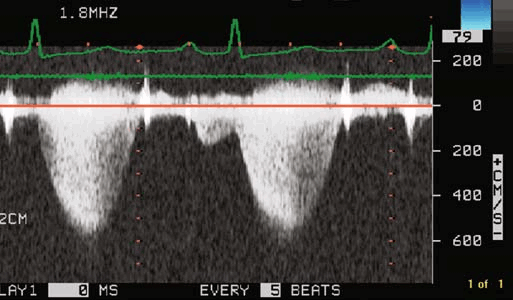

ЭКГ при стенозе устья легочной артерии выявляет признаки перегрузки правого желудочка, отклонение ЭОС вправо. При помощи эхокардиографии обнаруживается дилатация правого желудочка, постстенотическое расширение легочной артерии; допплерография позволяет выявить и определить разницу давления между правым желудочком и легочным стволом.

Путем зондирования правых отделов сердца устанавливается величина давления в правом желудочке и градиент давления между ним и легочной артерией. Данные вентрикулографии характеризуются увеличением полости правого желудочка, характерным замедлением исчезновения контраста из правого желудочка. Пациентам старше 40 лет и лицам, жалующимся на загрудинные боли, показана селективная коронарография.

- Катетеризация сердца. С целью измерения градиента давления между левым желудочком и аортой выполняется зондирование полостей сердца, которое позволяет косвенно судить о степени аортального стеноза.

Стеноз легочной артерии является наиболее часто встречающимся пороком развития сердца, который хорошо можно определить на эхокардиографии. Согласно статистике, этот порок вместе с атрезией легочной артерии составляет почти половину всех случаев врожденных пороков сердца. При этом сушение легочной артерии встречается по крайней мере в пять раз чаще, чем полная атрезия. Расположение, размеры и степень стеноза на эхокардиографии бывают разными. По данным эхокардиографии описываются следующие главные типы:

- Сужение инфундибулярной части правого желудочка мышечной пластинкой или фиброзным тяжем (так называемый инфундибулярный стеноз). В некоторых случаях гипертрофическая мышечная или соединительная ткань, создающая впечатление рубца, суживает большую часть инфундибулярного отдела сердца, так что он меняется на эхокардиографии в узкий канал разной длины. Только в редких случаях отмечается стеноз на всем протяжении инфундибулярного отдела. В большинстве случаев инфундибулярный отдел сохраняет коническую форму. С самого начала он постепенно сужается, так что его просвет уменьшается непосредственно под устьем легочной артерии, образуя небольшое отверстие (подклапанный инфундибулярный стеноз). Иногда через гипертрофированную мышечную ткань инфундибулярного отдела проходит несколько узких извитых канальцев неправильной формы, которые открываются в правый желудочек и соединяются друг с другом по направлению к устью легочной артерии. Гораздо чаще сужение распространяется на небольшую часть инфундибулярного отдела, либо в самом его начале (прединфундибулярный стеноз, или стеноз инфундибулярного устья), либо на любое место инфундибулярного отдела, начиная от его устья, вплоть до его конца, непосредственно под клапанами (инфундибулярный стеноз в прямом смысле слова, который может быть высоким, промежуточным или низким). В таком случае инфундибулярный отдел над местом сужения на эхокардиографии бывает расширенным и образует как бы добавочный третий желудочек, величина которого зависит от места сужения. Он достигает наибольших размеров при прединфундибулярном и при низком инфундибулярном стенозе. Таким образом возникает значительное выпячивание части инфундибулярного отдела в вентральном направлении, хорошо заметное эхокардиографическом исследовании. Стенка расширенной части инфундибулярного отдела между местом сужения и устьем легочной артерии может быть утолщенной, состоящей из мышечной ткани, либо утонченной, состоящей из фиброзной ткани.